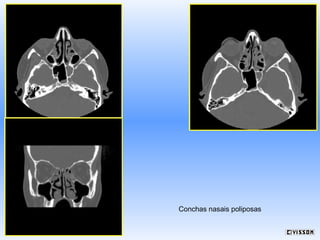

Conchas nasais poliposas